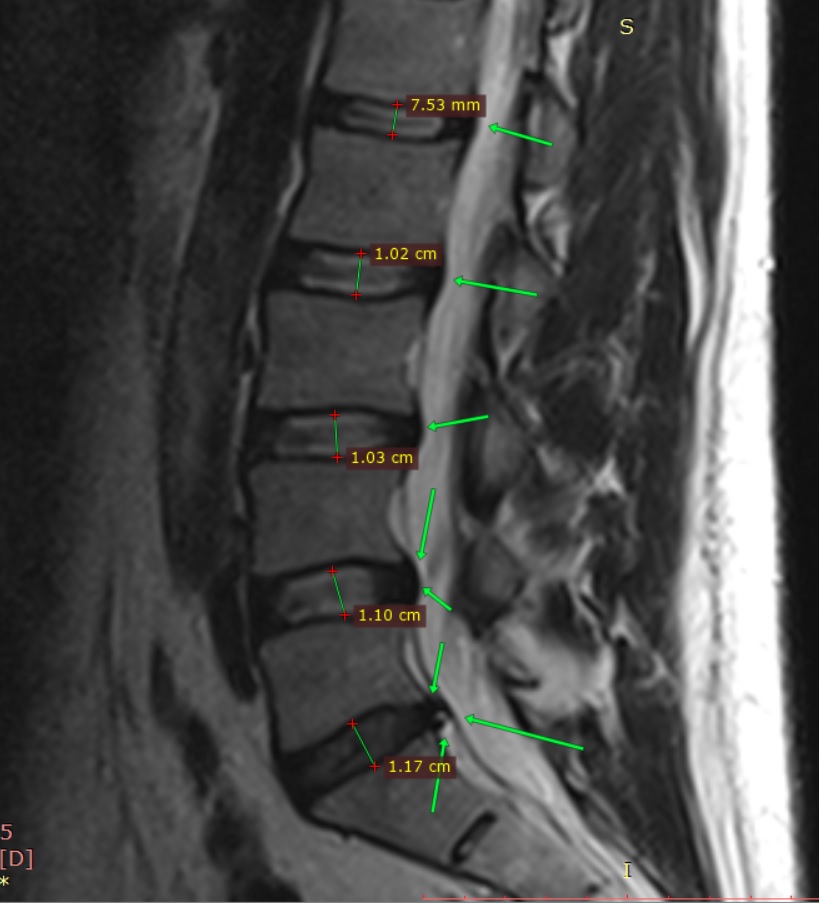

MMRLANDRYGGMR20[...].png 982Кб, 1024x1024

Хуйня у тебя, а не грыжа. Зацени мою:

L5 / L5 11 мм. Осенью боль была такая, что аж морфин прописывали и тот не до конца снимал. Теперь мне упражнения всю жизнь делать. Если все окей, то войду в ремиссию и опять буду и на веле и на лыжах горных катать. А пока работаю большую часть дня стоя, чтобы спину не нагружать. Хорошо, что и в офисе и дома столы с электро лифтом

В основном делаю лёжа на спине всякие. Ногами по всякому двигаю, таз поднимаю, итд. Всякие на четвереньках прогибы туда сюда. Реально работают упражнения. Мой ортопед когда впервые мой снимок увидел, думал, что это снимок лежачего больного.